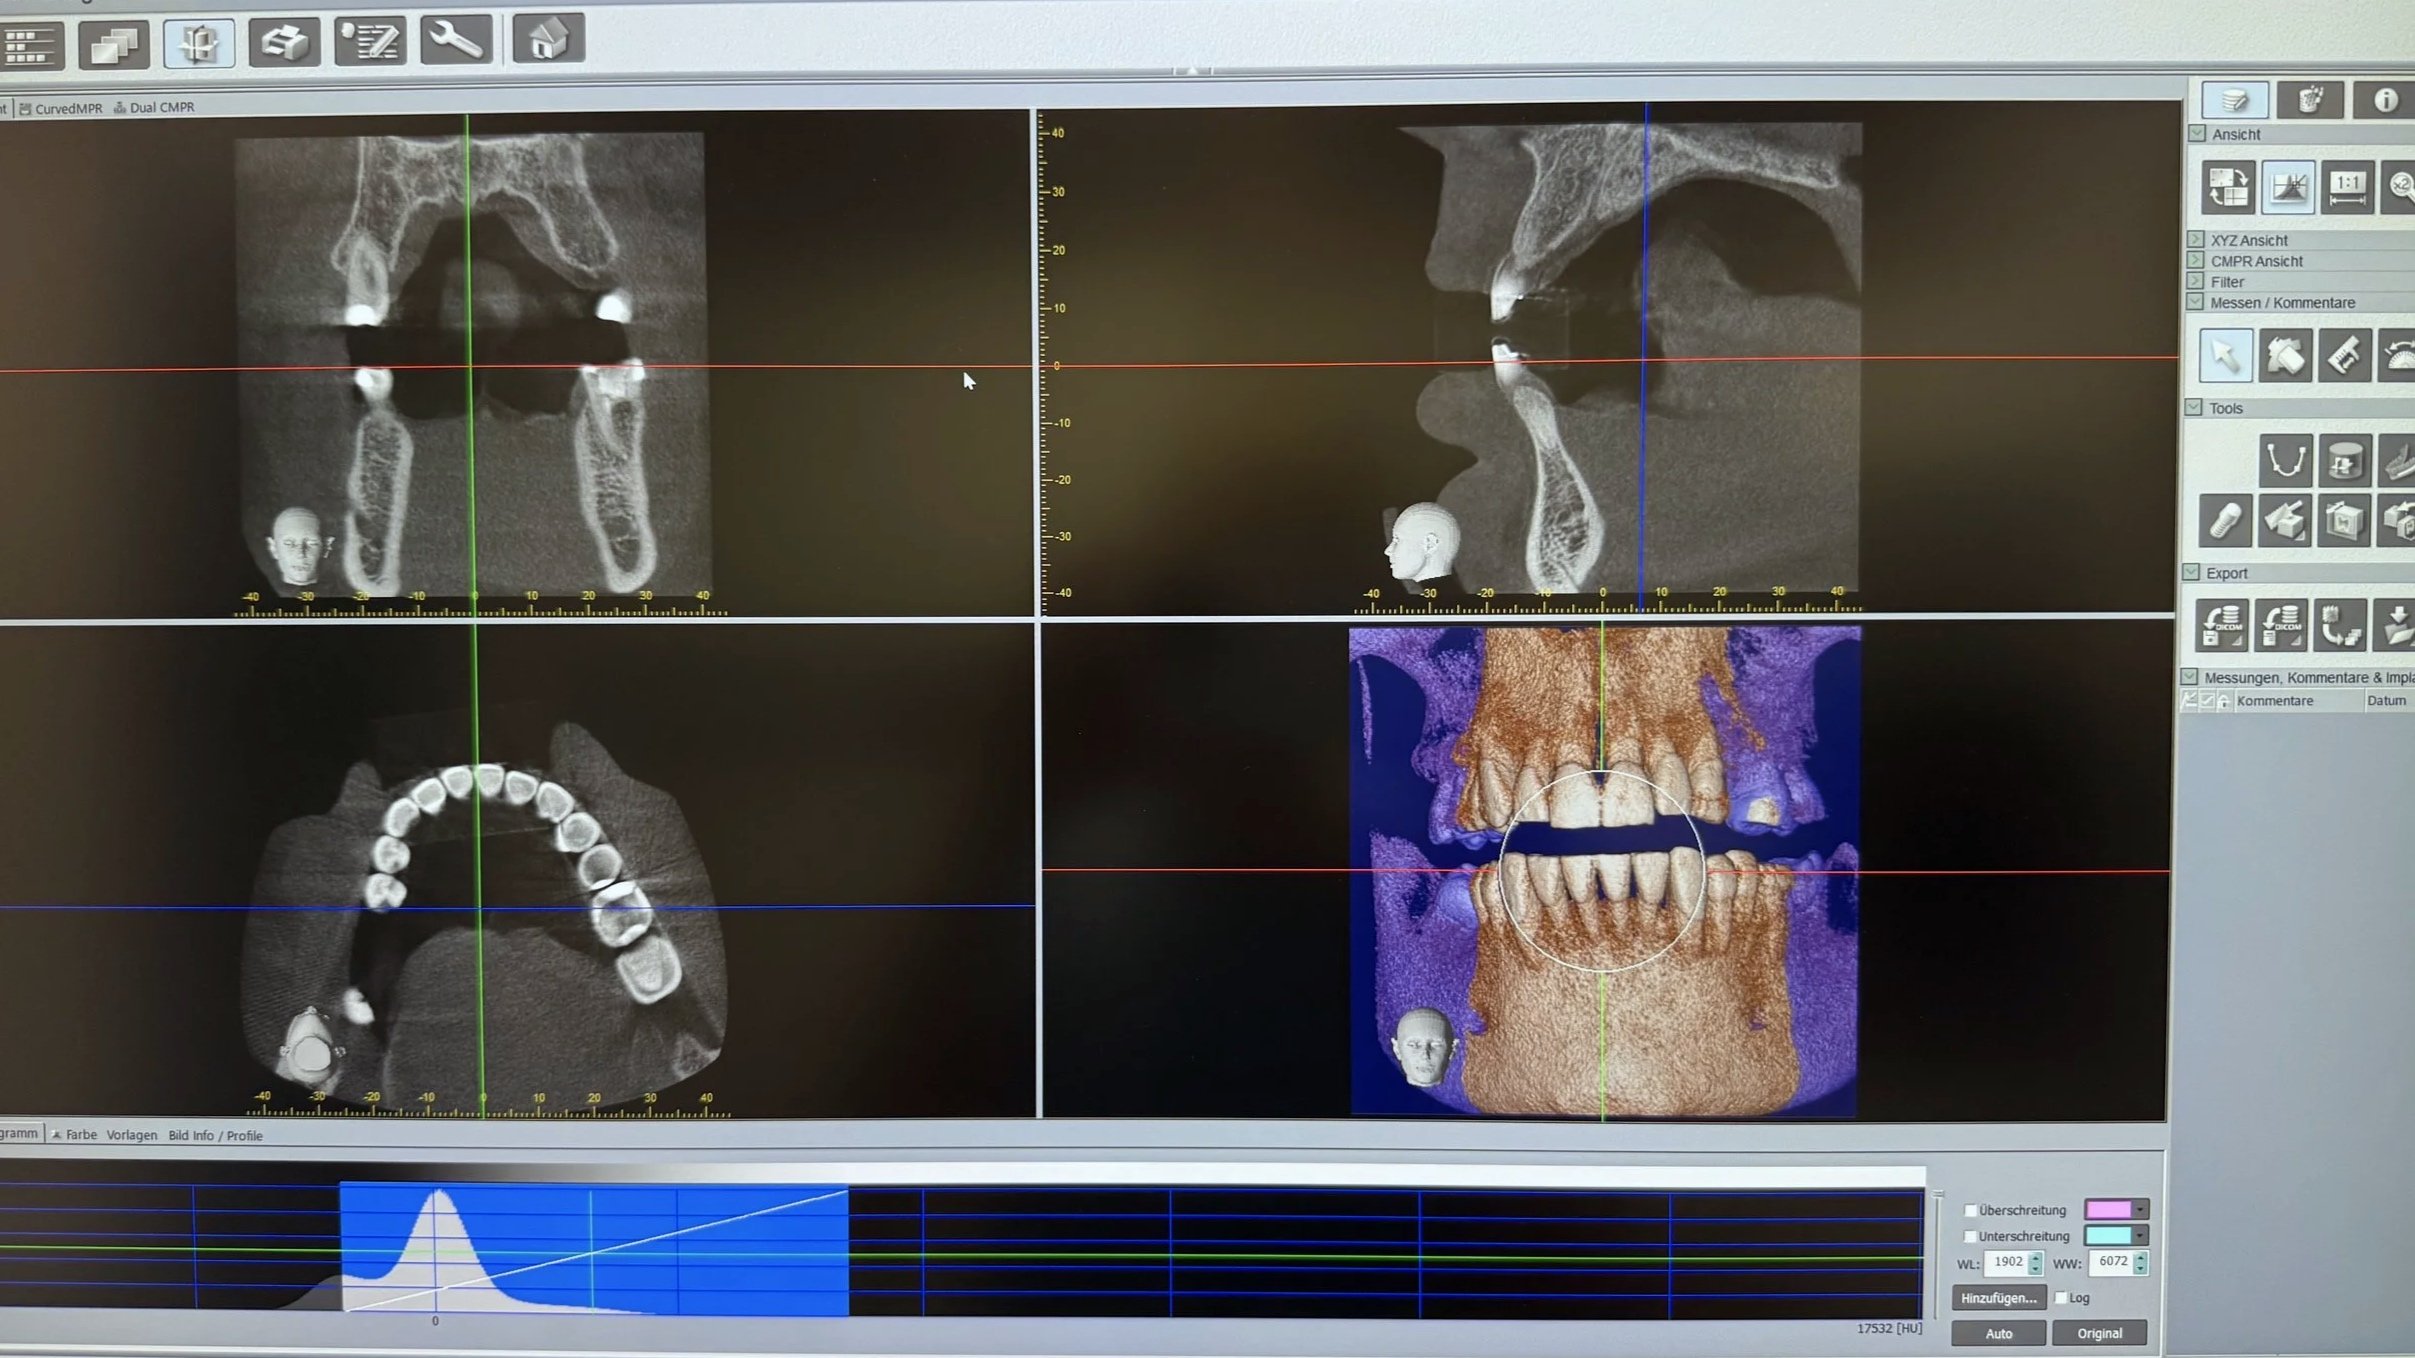

Dental X-ray scans showing 3D models of teeth and jawbones aligned in four quadrants on a medical imaging screen.

• In unserer Praxis nutzen wir die digitale Volumentomographie (DVT), eine moderne Methode, die 3D-Röntgenbilder von Zähnen, Kiefern und umgebenden Bereichen erstellt. Dadurch können wir präzise Diagnosen stellen und Behandlungen wie Implantate, Wurzelkanalbehandlungen oder Weisheitszahnentfernungen besser planen. Die DVT zeigt feine Details, macht die Behandlung sicherer und schneller. Die Strahlenbelastung ist dabei viel geringer als bei herkömmlichen CTs, und die Untersuchung dauert nur wenige Sekunden. So sorgen wir für genaue Diagnosen und schonende, individuelle Therapien, die Ihre Zahngesundheit langfristig fördern.